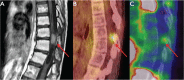

He then received metronomic vinblastine at 2mg/m2/w and a complete PET-scan negativity was achieved after 12 months of the low-dose vinblastine treatment. At last follow up, she is still in CR, 20 months after completion of therapy.

It can be speculated that low-dose vinblastine acted both as an antiangiogenic agent and as a dendritic cells activator.